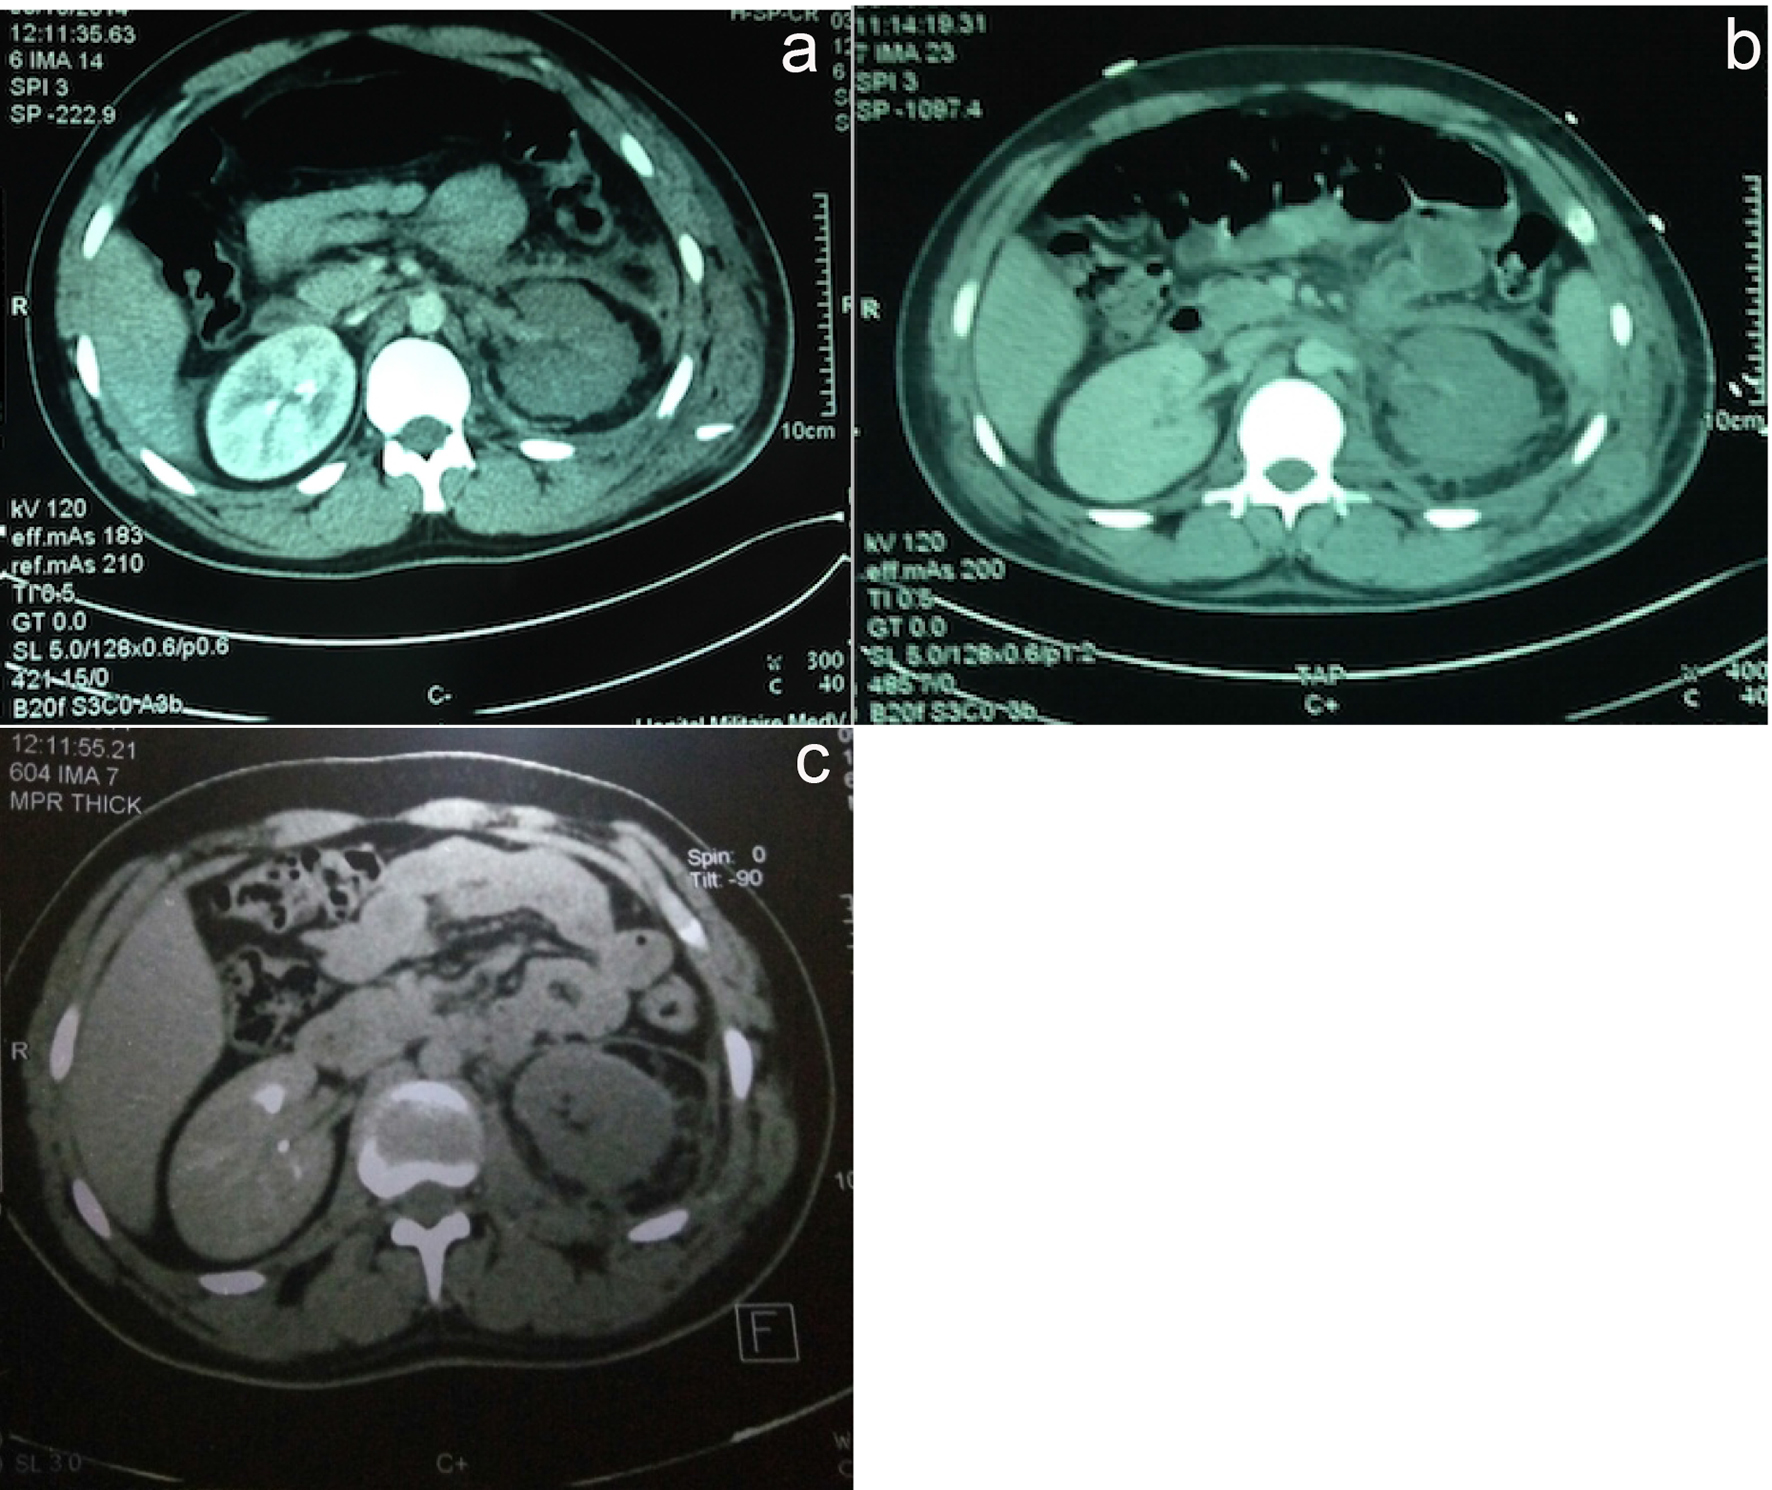

While the patient remained hemodynamically stable and after multidisciplinary consultation (urologists, radiologists and resuscitators), considering the young age of the patient and the location of the lesion, a surgical abstention was decided, with strict and regular monitoring by blood counts twice daily to detect a possible deglobulization. And in this context, the patient received only 2 units of packed red blood cells. A repeat CT angiogram performed at J3, J7 and J30 post-injury revealed a decrease in the retroperitoneal hematoma (Fig. 2).

![]() Click for large image | Figure 2. CT angiogram performed at J3 (a), J7 (b) and J30 (c) post-injury. |